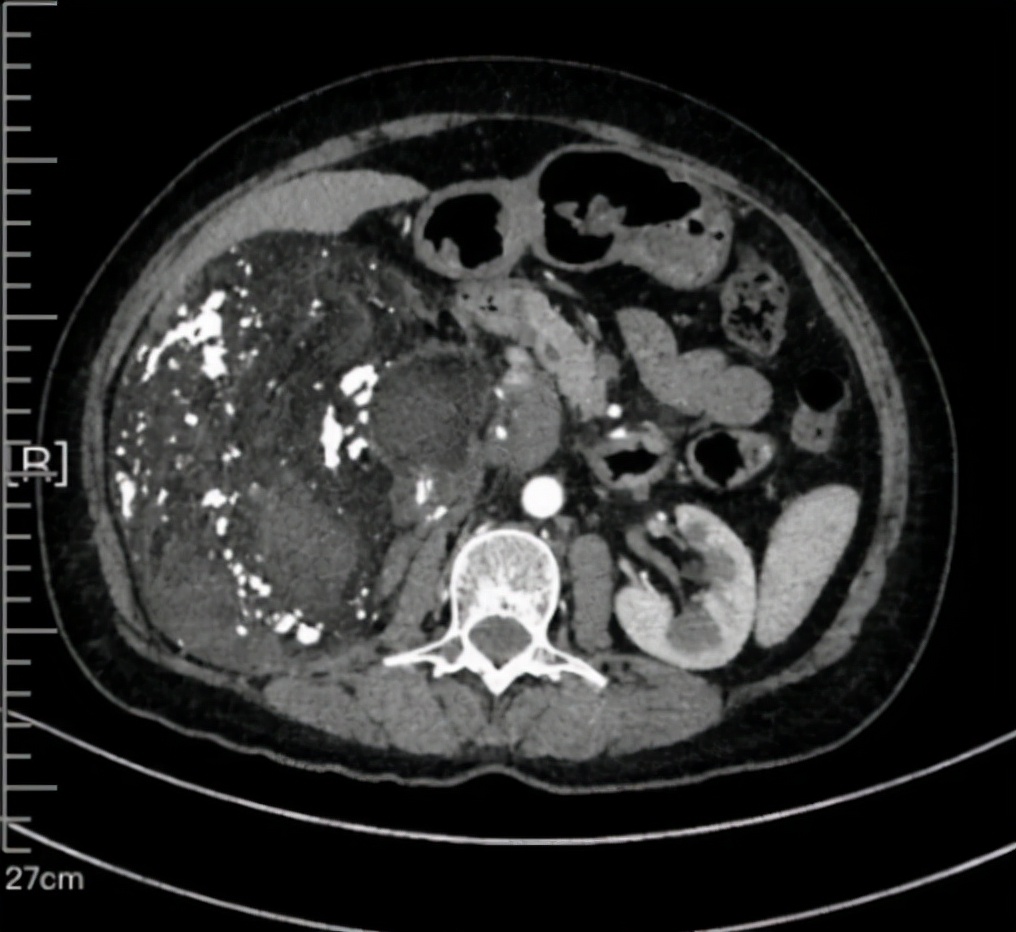

这个患者表现为右侧腹部后腹膜巨大肿瘤,上级侵犯到第二肝门,压迫下腔静脉和肝右静脉,右侧压迫下腔静脉,肿瘤侵犯下腔静脉上下,右侧侵犯肾门。肿瘤最右侧在腹主动脉左侧,直径超过25公分,压迫结肠十二指肠等。

术前